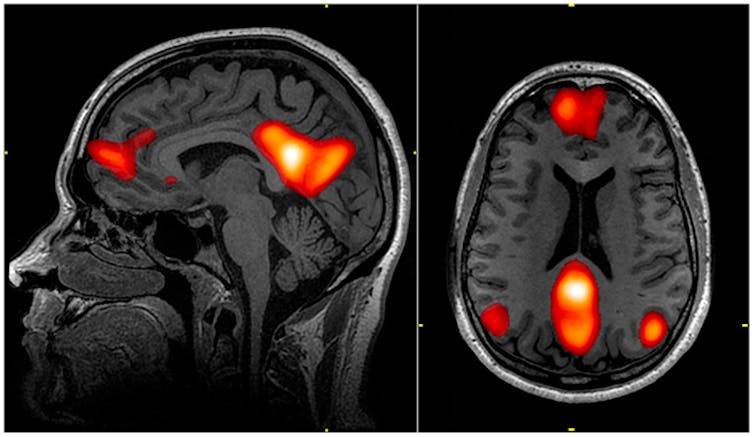

Previous studies, using functional MRI (fMRI) brain scanning, have shown that psilocybin seems to reduce activity in the medial prefrontal cortex, an area of the brain that helps regulate a number of cognitive functions, including attention, inhibitory control, habits and memory. The compound also decreases connections between this area and the posterior cingulate cortex, an area that may play a role in regulating memory and emotions.

An active connection between these two brain areas is normally a feature of the brain’s “default mode network”. This network is active when we rest and focus internally, perhaps reminiscing about the past, envisioning the future or thinking about ourselves or others. By reducing the activity of the network, psilocybin may well be removing the constraints of the internal “self” – with users reporting an “opened mind” with increased perception of the world around them.

Just one day after the first dose of psilocybin, fMRI measures revealed an overall increase in connectivity between the brain’s various networks, which are typically reduced in those with severe depression. The default mode network was simultaneously reduced, while connectivity between it and other networks was increased – backing up previous, smaller studies.

MRI scan showing the default mode network. – Wikipedia